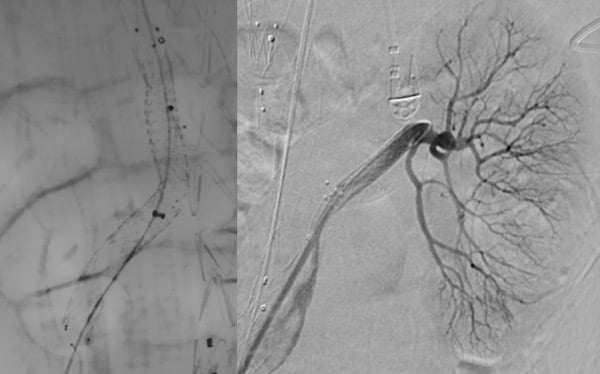

Step 1: TEVAR

Step 2: SMA and LRA stenting

(30 days after step 1)

Step 3: bilateral iliac branch

(45 days after step 2)

Step 4:

(30 days after step 3)

- RRA stenting

- Celiac trunk

Cannulation

Failure

↓

Branch

Embolisation